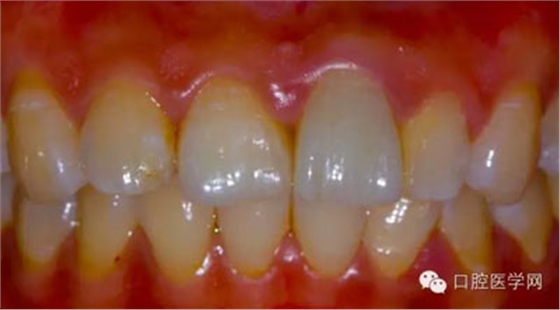

1、術(shù)前比色照

將比色照的飽和度調(diào)到最高有助于牙齒道飽和度選擇